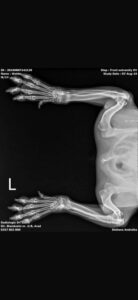

His left front paw turns out a little more sideways than the other one. He’s had X-rays and all is in order, no accident or injury, he was born like this. It doesn’t bother him as he loves to go for walks, run and play.